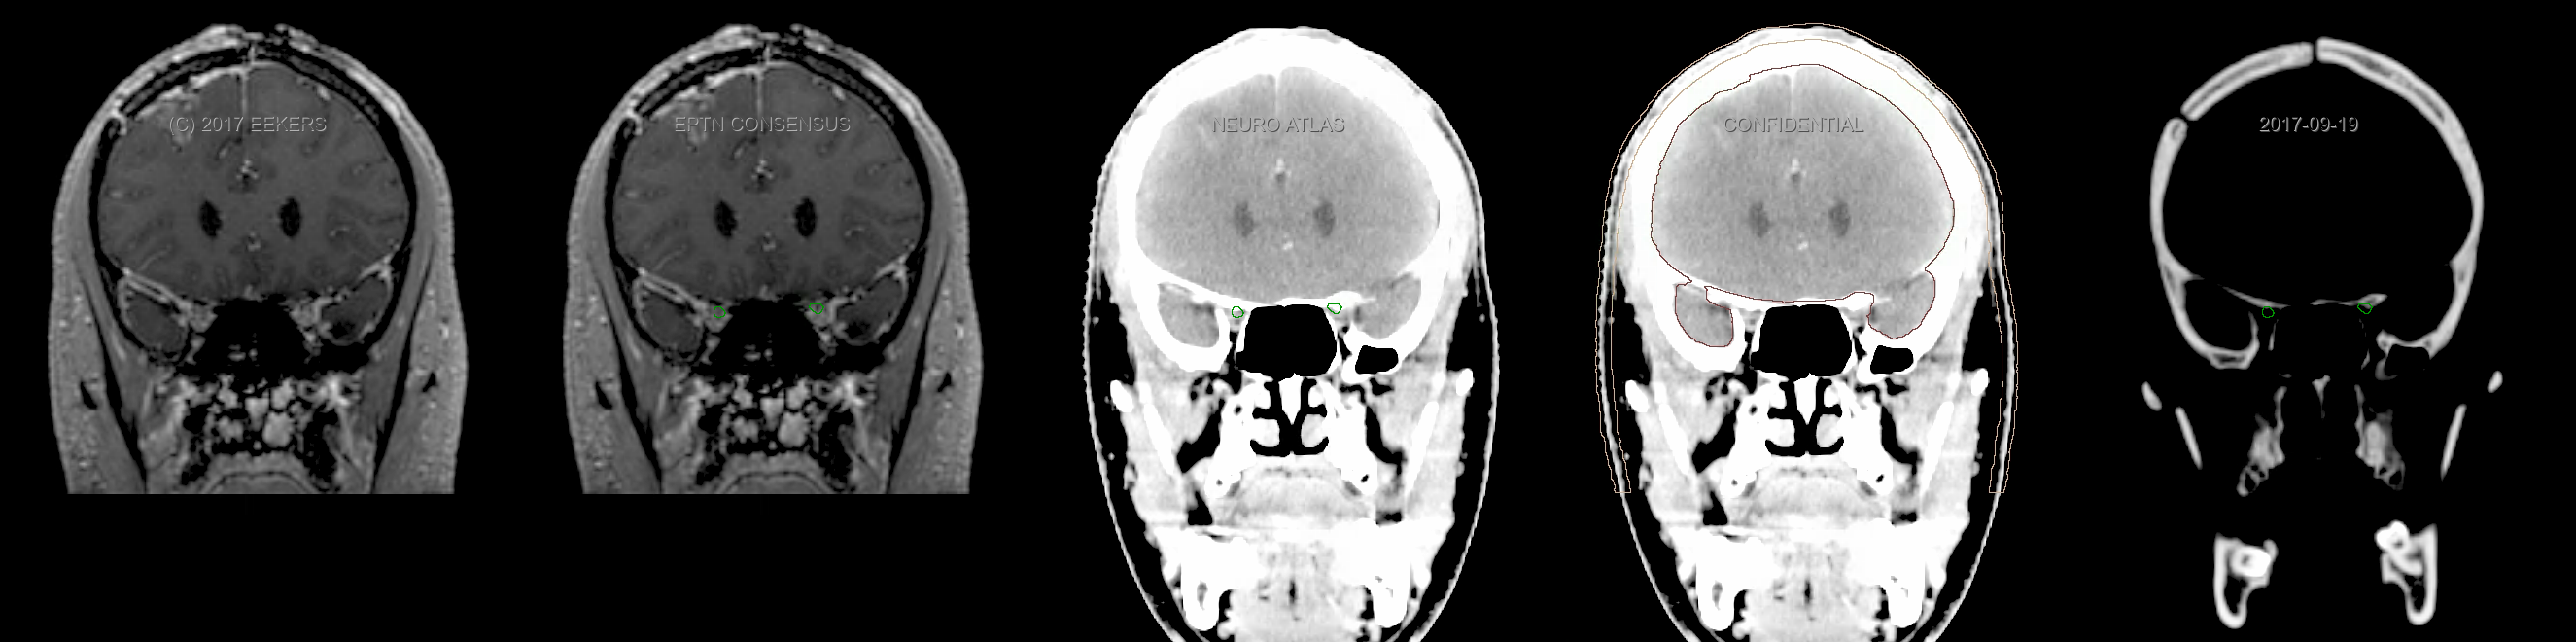

Three-dimensional delineation of the fifteen consensus OARs for neuro-oncology are shown on CT and 3 Tesla (3T) MR images (slice thickness 1 mm with intravenous contrast agent). All are presented in transversal, sagittal and coronal view.

From left to right: MR without structures, MR with structures, CT (WW/WL 120/40) with structures, CT (WW/WL 120/40) with Brain and Brainstem Surface, CT (WW/WL 1500/120)with structures